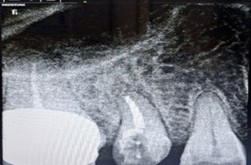

A 51-year-old woman presented with a 15-day history of persistent pain in the right mandibular posterior region. Her dental record showed multiple failed restoration attempts and an incomplete root canal on tooth 46, yet her symptoms persisted. Clinical examination and intraoral periapical radiography revealed furcation involvement, a large periapical radiolucency, and a perforation in the pulp chamber floor.

Despite a guarded prognosis for tooth survival, we performed thorough canal disinfection and placed Metapex as an intracanal medicament for four weeks. The patient reported no inter-appointment discomfort. At the subsequent visit, radiographs confirmed complete resolution of the periapical lesion, and root canal obturation was successfully completed.

Figure 1: Pre operative IOPA wrt 46 showing incomplete root canal treatment, with furcation involvement, a large periapical lesion and perforation of pulp chamber floor.

Figure 3: Post 4 weeks, complete resolution of periapical lesion. Figure 4: Post obturation IOPA after 4 weeks.

Figure 4: Post obturation IOPA after 4 weeks.